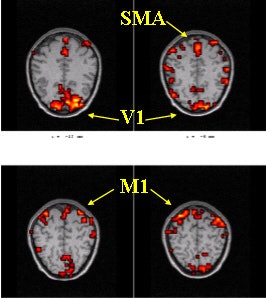

The areas of investigation were the left and right primary motor cortices (M1) and the primary visual cortex (V1). Above, a baseline fMRI scan during a visually cued motor task. Below, the same areas scanned after caffeine. Significant changes were seen in the signal change of the BOLD response. Images courtesy of Todd Parrish, Ph.D.

The average BOLD signal amplitude response was determined from three areas of investigation, including the left and right primary motor cortex and the primary visual cortex. Additional analysis was done to measure the signal-to-noise ratio (SNR) in the nonactivated BOLD data, both before and after treatment.

After the administration of caffeine, the average percentage signal change of the BOLD response, relative to baseline, showed significant changes in both motor and visual areas, with the motor region exhibiting a 37% signal change. In addition, there was a notable decrease in the SNR following caffeine, with an average decrease of 4.4%. Finally, the average perfusion level decreased by 11%-13% without a change in performance as measured by reaction time, the group concluded.